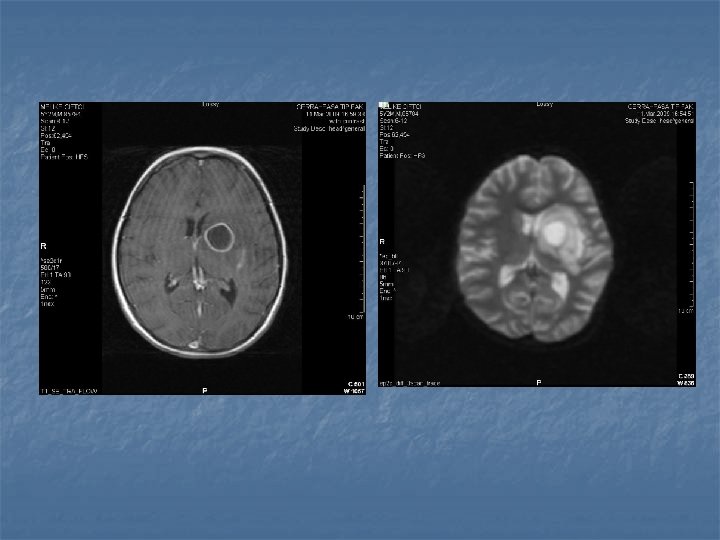

Medüller abse- 4 è Klinik è Akut è infeksiyon bulguları, ense sertliği, lokal ağrı, transvers myelite bağlı nörolojik bulgular è Kronik è İntramedüller tümörü taklid eden bulgular è Tanı è Direkt grafi, likor incelemesi, Lökositoz è MRI è T 1 periferik kontrast tutulumu è T 2 periferik hipointansite + santral hiperintansite